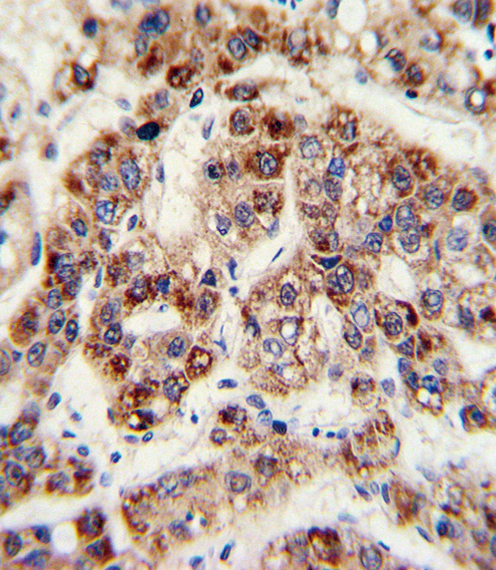

IHC (Immunohiostchemistry)

(Formalin-fixed and paraffin-embedded human hepatoarcinoma with OTC Antibody (Center), which was peroxidase-conjugated to the secondary antibody, followed by DAB staining. This data demonstrates the use of this antibody for immunohistochemistry; clinical relevance has not been evaluated.)